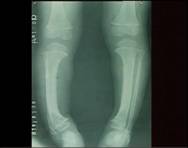

X線檢查

X線改變以骨骼發育較快的長骨為明顯,尤以尺橈骨遠端及脛腓骨近端更為明顯。

(2)下肢畸形“O”形腿(膝內翻),或“X”形腿(膝外翻)。

常見於3個月至2歲的幼兒。有明顯的夜驚、多汗、煩躁不安等症狀。同時可有中度的骨骺改變體徵。X線片可見臨時鈣化帶模糊消失,乾骺端增寬,邊緣不整呈雲絮狀,毛刷狀或杯口狀,骨骺軟骨加寬。血鈣、血磷均降低,鹼性磷酸酶增高。

多見於3歲以後的小兒。經治療或自然恢復,症狀消失,骨骼改變不再進展。X線及血生化檢查正常,僅留有不同程度的骨骼畸形。